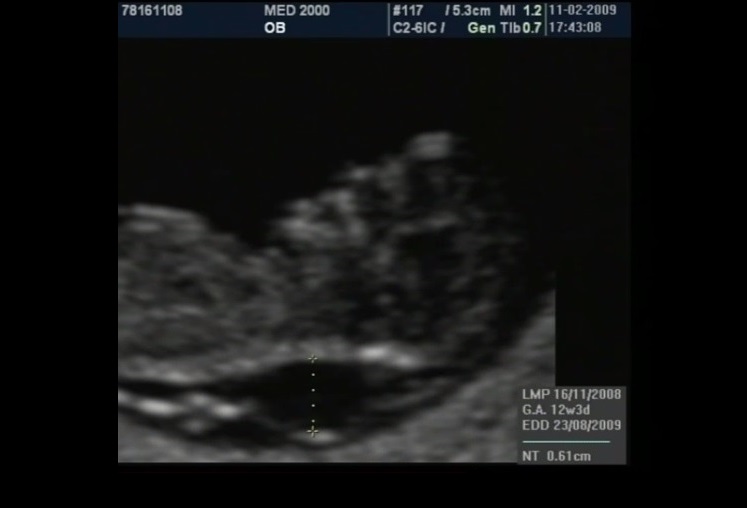

La translucenza nucale è un marker rilevabile tra le 11 settimane + 0 gg. e 13 settimane + 6 gg. di gestazione, più precisamente in un range del CRL compreso tra 45 mm. e 84 mm. Essa appare caratterizzata ecograficamente dall'accumulo sottocutaneo di fluido dietro il collo fetale nel primo trimestre di gravidanza. La Fetal Medicine Foundation (FMF) di Londra ha dettato i criteri da adottare per una corretta misurazione della NT:

- posizionamento dei calipers "on to on": i cursori devono essere posizionati sui bordi interni delle linee che delimitano lo spazio della translucenza nucale senza che le linee orizzontali dei cursori protudano in questo spazio (vedasi immagine)

- la misurazione deve essere eseguita in corrispondenza della parte più ampia della Translucenza

Si è osservato che nei feti sani lo spessore della NT tende ad aumentare con l'incremento del CRL; di conseguenza anche i valori soglia della NT cambiano col variare dei valori del CRL: a 11 settimane con un CRL di 45 mm. i valori possono variare da 1,2 mm. (50° percentile) a 2,1 mm. (95° percentile), mentre a 13 sett. + 6 gg. con un CRL di 84 mm., i valori possono variare da 1,9 mm. (50° percentile) a 2,7 mm. (95° percentile); il 99° percentile non varia col CRL ed è circa 3,5 mm. Si intende per translucenza nucale aumentata uno spessore di NT al disopra del 95° percentile. Con un software dedicato che prende in considerazione NT, CRL, età materna e Frequenza Cardiaca Fetale (FHR), con un cut-off attualmente di 1/100 (Fetal Medicine Foundation) è possibile calcolare il rischio di anomalie cromosomiche con una sensibilità di circa il 90% ed una percentuale di falsi positivi di circa il 5%. La FHR assume notevole importanza nello screening della Trisomia 13: infatti circa l'85% dei feti con Trisomia 13 hanno una frequenza cardiaca al disopra del 95° percentile; nella Trisomia 21 solo il 15% dei feti ha un lieve aumento della FHR oltre il 95° percentile, mentre nella Trisomia 18 solo il 15% dei feti ha una lieve diminuzione della FHR al disotto del 5° percentile.